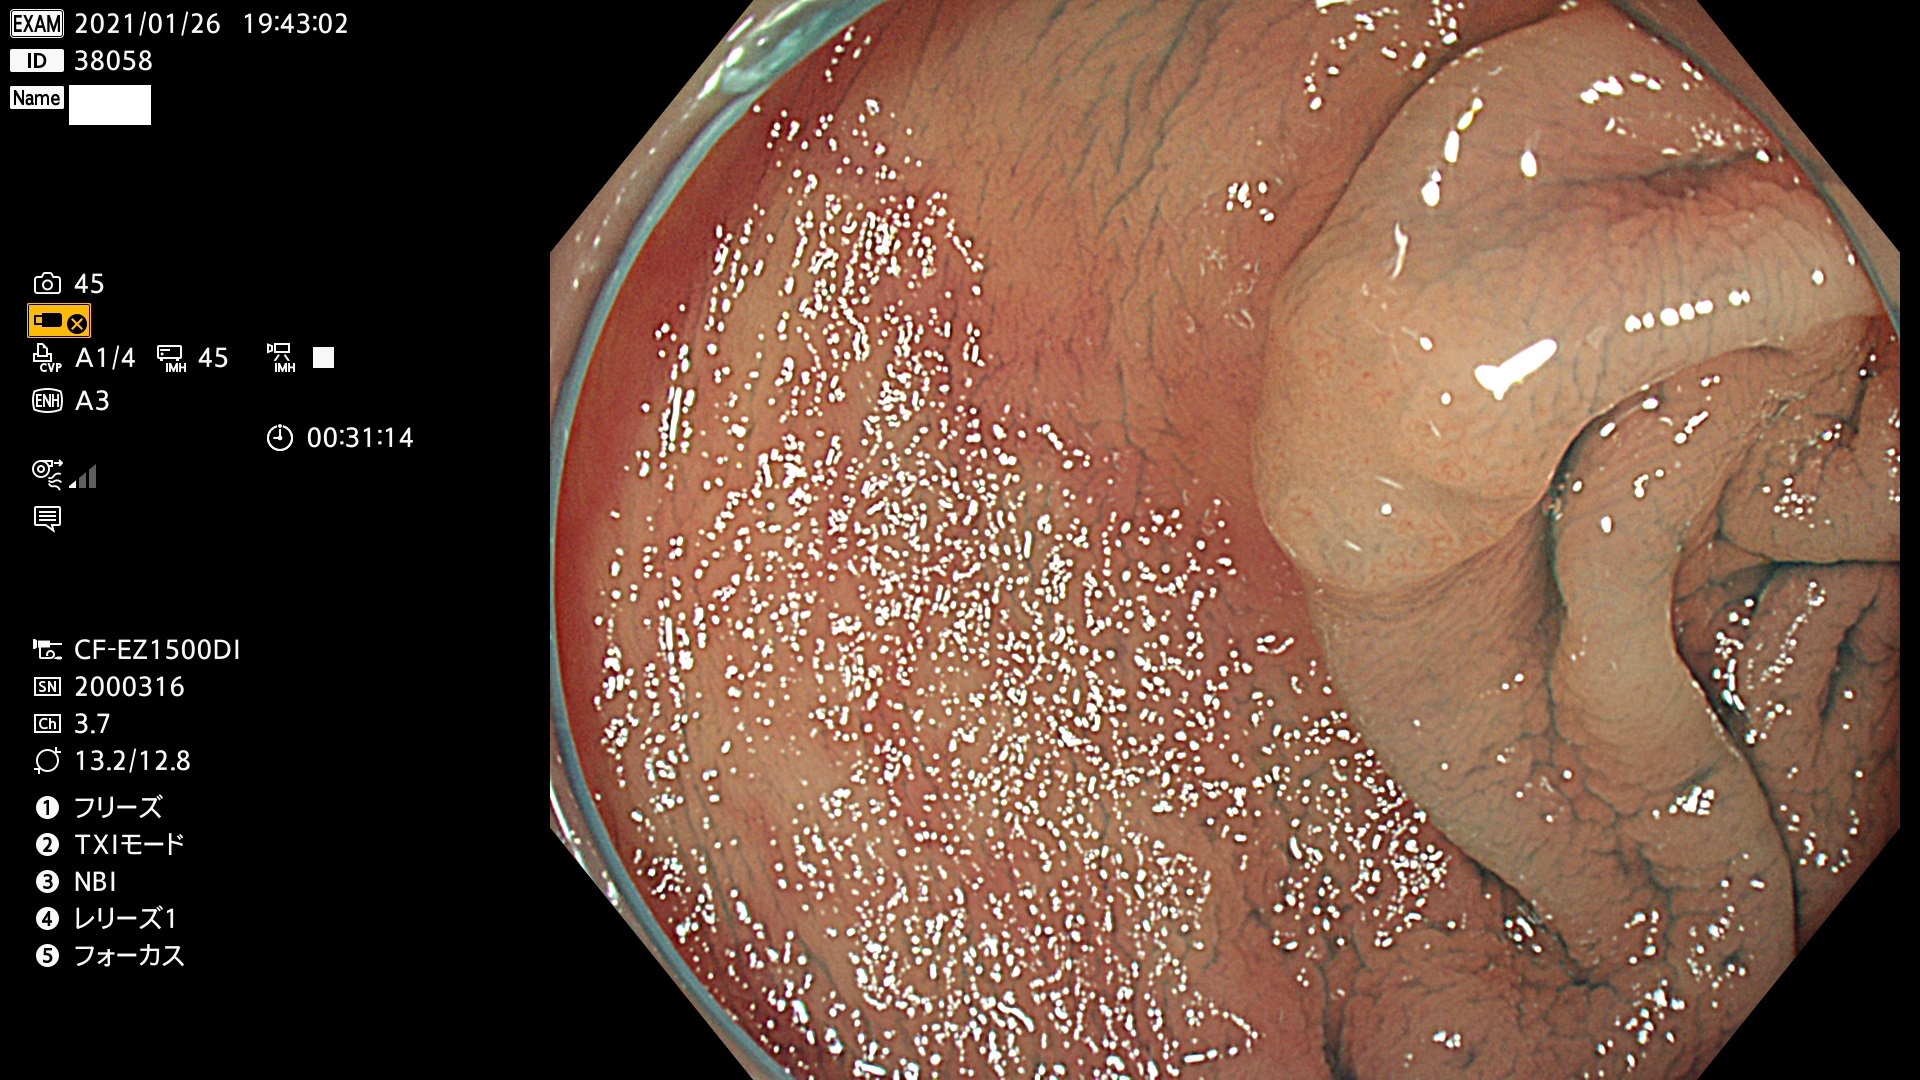

38001 38002 38003 38004 38006(SSAPのみ) 38007 38008 38009 38010 38012 38013 38014 38016 38018 38020 38021 38025 38026 38029 38032 38033 38034 38035 38036 38037(SSAPのみ) 38039 38043 38044 38048 38049 38050 38052 38055 38056 38057 38058 38059 38064(SSAPのみ) 38065 38068 38069 38070 38071 38072 38074 38075 38076 38078 38079 38080 38082 38083 38084 38085(SSAPのみ) 38086 38087 38088 38089 38090 38091 38092 38093 38094 38097 38098 38099

発見困難で危険性の高い平坦型病変(上記100名より抽出)